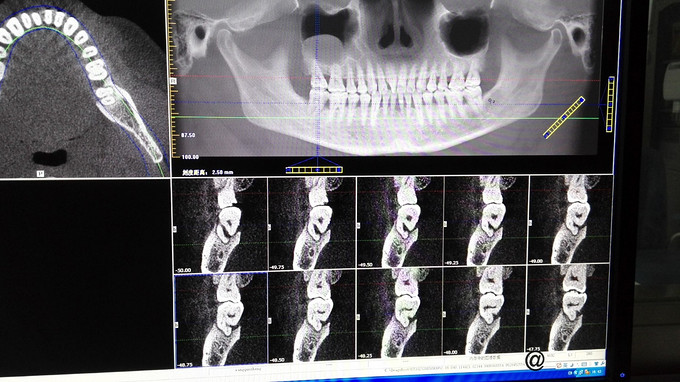

检查:右下7牙冠完整,近龈缘可见一突起脓包,少量脓血分泌物溢出,PD=10mm,余位点PD=3mm左右,叩痛(+),松动I度,电活力测试较正常牙迟钝。X线示:右下7牙槽骨水平吸收至根中,根分歧下低密度影像,远中根管增宽,可以根折。复拍CT:右下7根分歧下低密度影像,未达根尖,两根在舌侧融合,唇侧分开,唇侧无根柱,未见根折。

诊断:右下7牙周牙髓联合病变 治疗计划:右下7RCT+牙周基础治疗